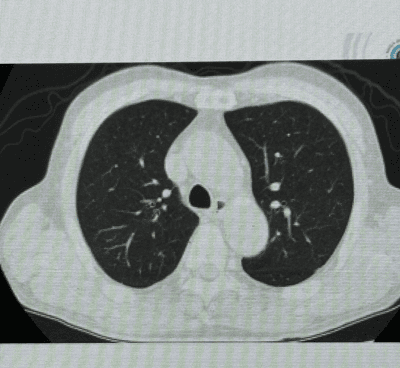

実は、肺という臓器には結構な奥行きがあります。下の肺の断面図を見ていただくと分かるように、正面(写真上側)から見た横幅よりも奥行きの方が長くなっています。